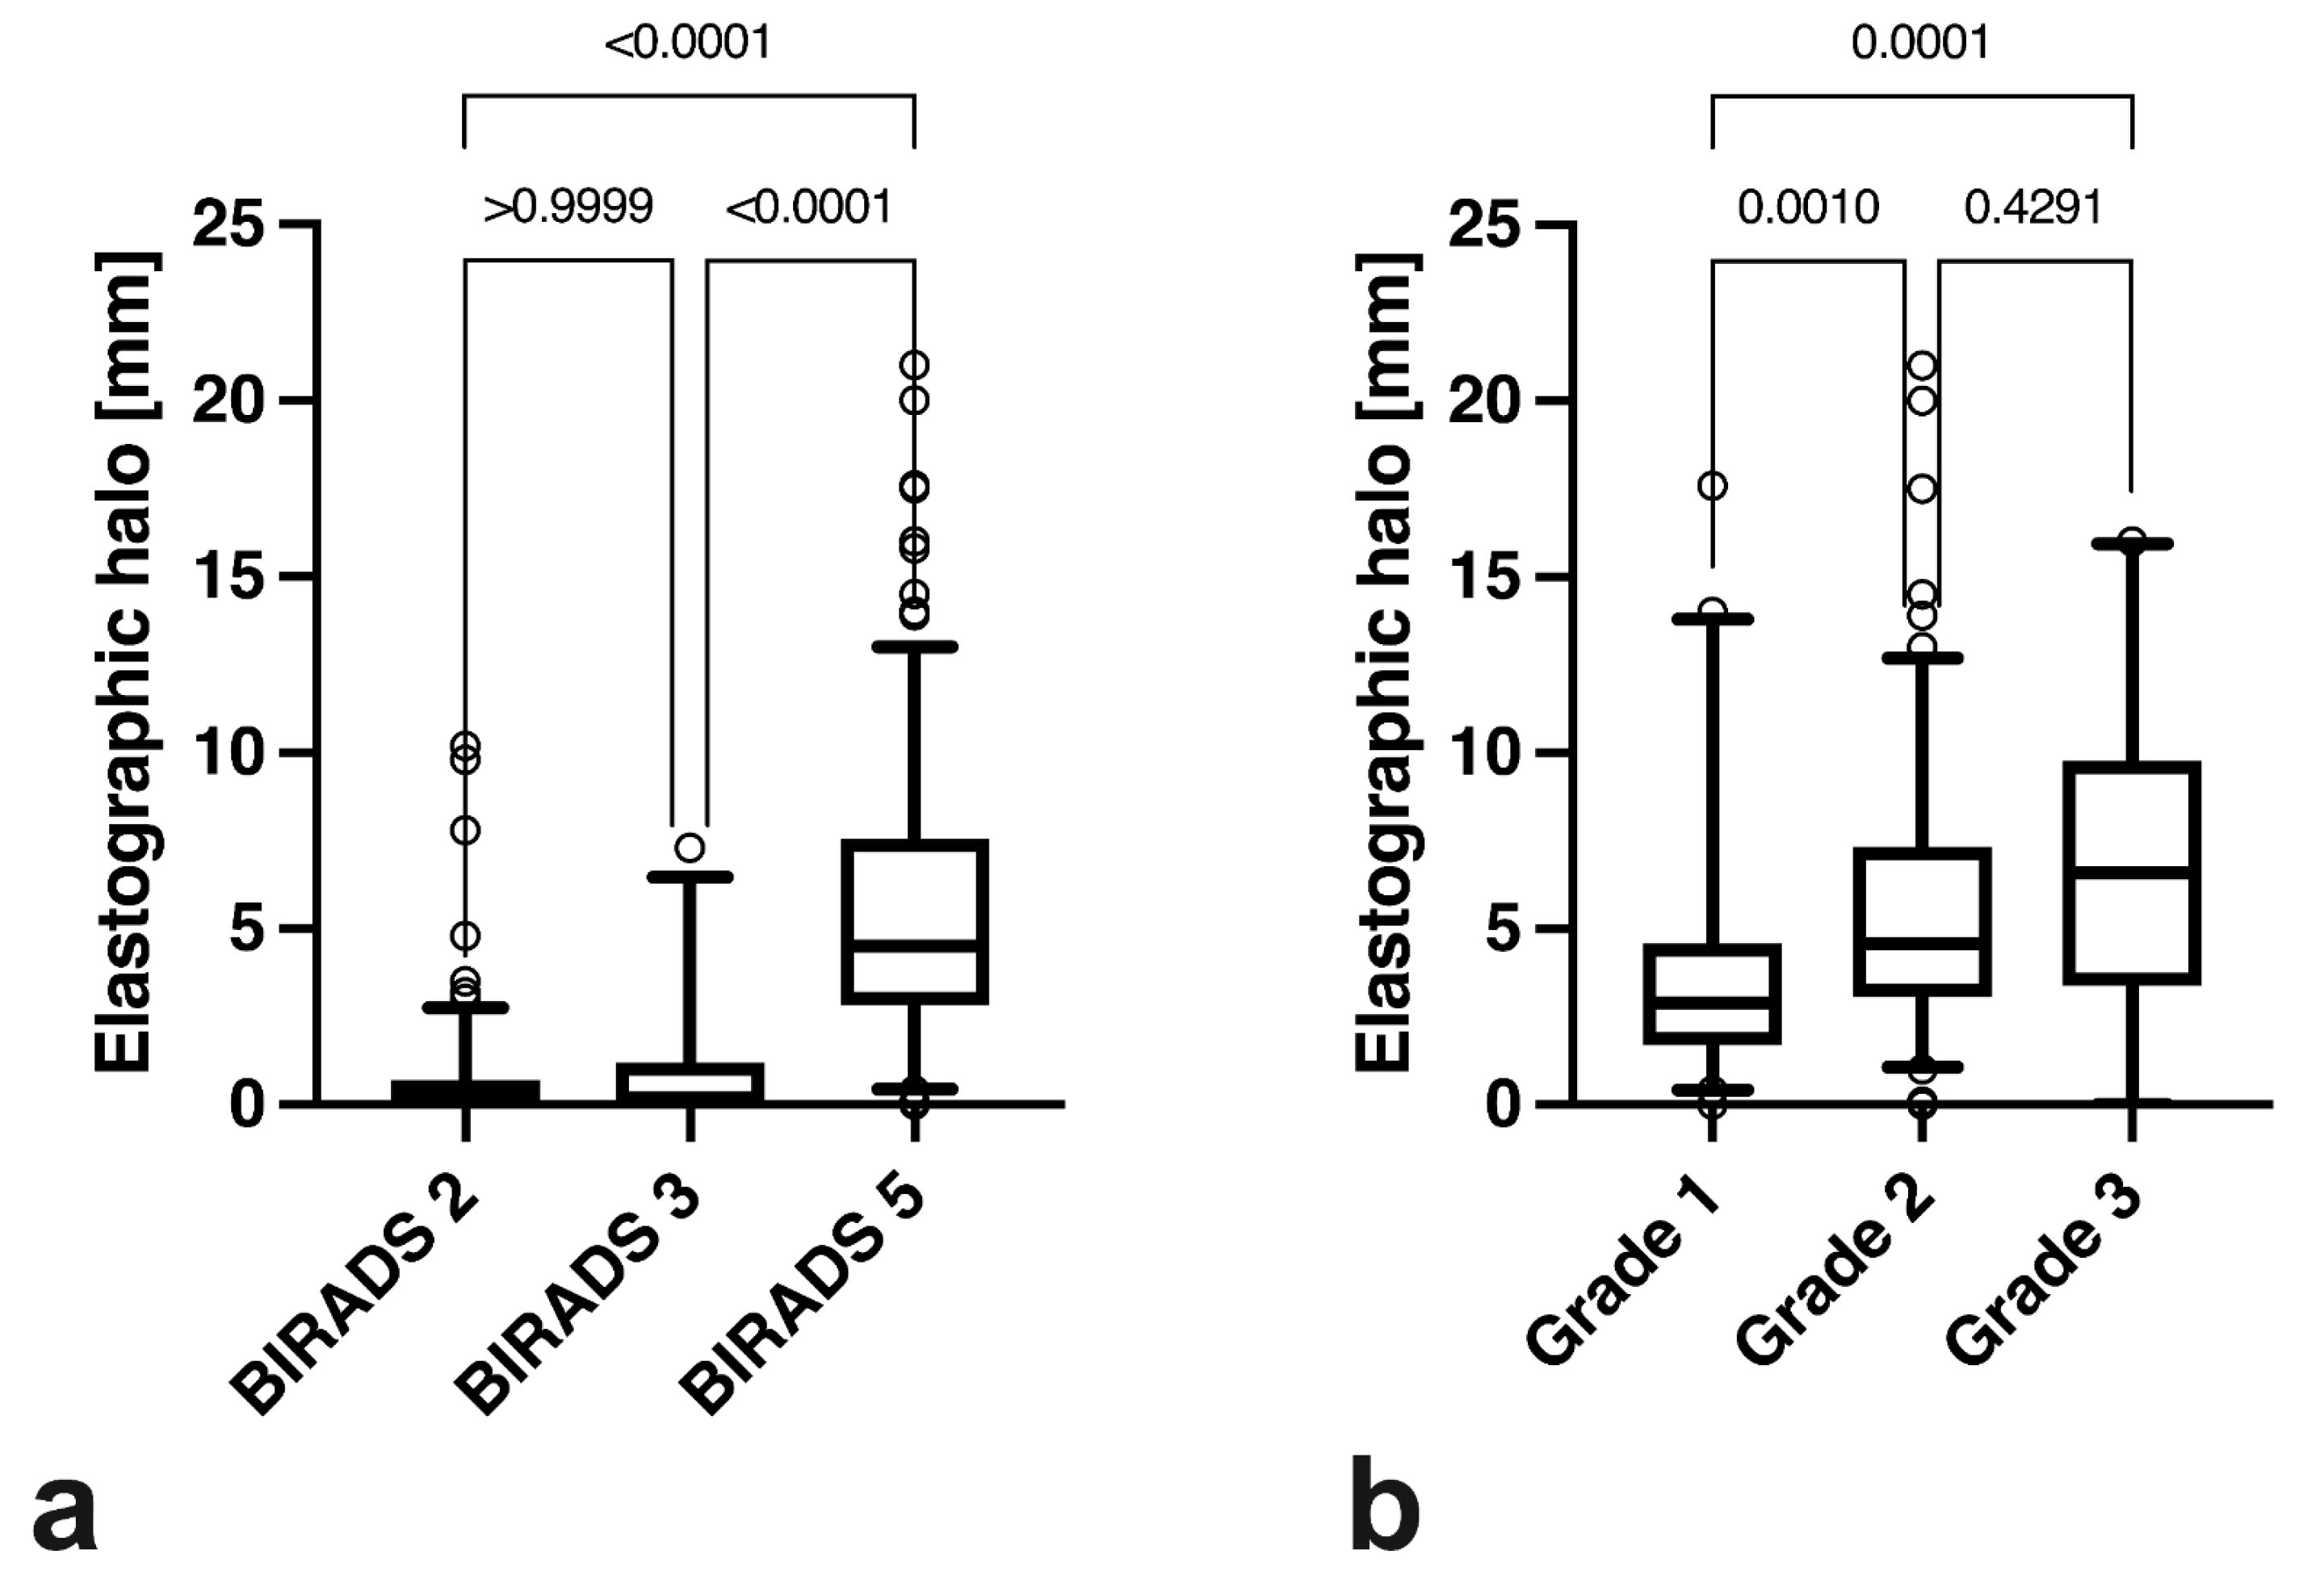

| SEPHmax | 0.6 ± 1.4 mm | 0.9 ± 1.4 mm | 5.5 ± 3.9 mm | >0.9999/<0.0001/<0.0001 |

| Tumour grade | Grade I | Grade 2 | Grade 3 | p-values $ |

| SEPHmax | 4.0 ± 3.9 mm | 5.6 ± 3.6 mm | 6.8 ± 4.2 mm | 0.001/0.0001/0.4291 |